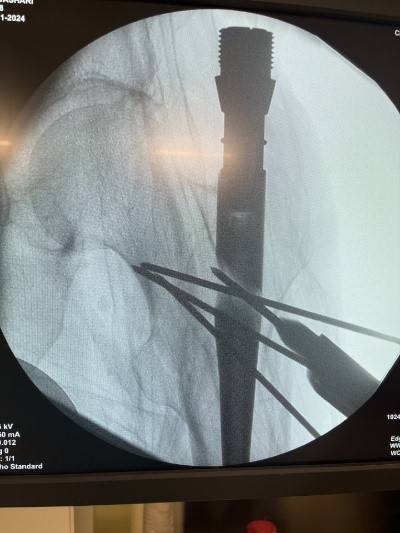

Hip fractures in the elderly are quite frequent and result in a high morbimortality rate [3,4]. The functional impairment leads to considerable social as well as economic implications due to the inability of the patients to perform their daily activities [5,6]. The morbidity of unilateral hip fractures ranges from 40 to 50% in women and from 13 to 22% in men [7], which is quite a high incidence. Contrary to this, simultaneous bilateral PFFs are not that common; therefore, there is a lack of data in the literature regarding the management of these injuries. According to Grisoni et al., over the period of 10 years, only eight cases were reported, with a frequency of 0.3% of the total number of hip fractures [8]. Furthermore, Verma et al. over the period of 3 years presented only four cases of simultaneous bilateral PFF with a rate of 0.24% [9]. Because of the low incidence of these types of injuries, there is no established, reliable treatment protocol yet, making these patients unique and demanding in the treatment process. Rodriguez-Zamorano has reviewed and analyzed the corresponding literature related to simultaneous bilateral PFF, and they have identified three patient profiles: “(i) Young patients involved in a traffic accident with multiple associated injuries, for which the definitive surgical intervention was sometimes delayed, having an impact on the overall survival. (ii) Patients aged 65–75 years old with fractures in the context of high-energy accidents. (iii) Patients over 80 years who sustain fragility fractures after casual falls from their height”[1]. An interesting fact that must be emphasized here is that our case does not fit into any of the above-mentioned patient profiles because the patient is above 85 years old and has sustained a high-energy trauma. In this course of events, this case would make an independent “fourth” profile of patients with simultaneous bilateral PFF. There are different approaches regarding the surgical treatment of simultaneous bilateral extracapsular hip fractures. We decided on proceeding with intramedullary fixation bilaterally since it offers better results compared to extramedullary fixation – shorter intraoperative time, smaller surgical wound, lower infection rate, less blood loss, and earlier weight bearing. There is an ongoing debate about whether to ream the intramedullary canal. While reaming allows usage of a thicker implant – thus biomechanically more stable fixation, on the other hand, it increases intraoperative time and the risk of fat embolism syndrome, especially in patients with bilateral proximal fractures. Furthermore, adult respiratory distress syndrome is considered significantly higher in bilateral fractures [10]. In our case, we decided not to use reaming in either of the fractures. Closed reduction and percutaneous K-wires were used for the fixation of the right intertrochanteric fracture (Fig. 6), whereas open reduction and percutaneous K-wires were used for the fixation of the left subtrochanteric fractures since closed reduction was unsatisfying (Fig. 7).

Figure 7: Left hip. Open reduction and K-wires.